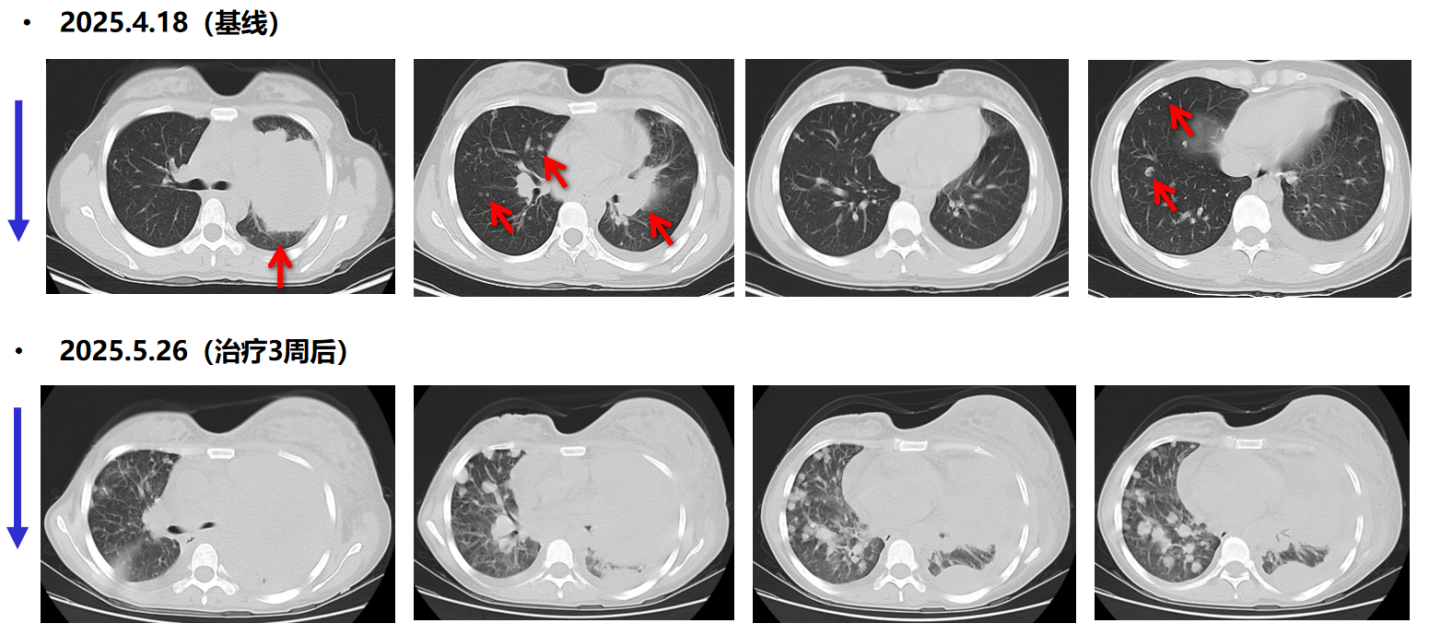

一线治疗:患者PD-L1高表达(≥50%),无常见敏感驱动基因(EGFR/ALK/ROS1阴性),入组临床研究。2025-05-06 给予C1D1治疗: PD-1/TIGIT双抗 静滴 d1,q3w;辅以支持治疗。

疗效评估:治疗仅3周后,患者病情迅速恶化。自觉胸闷加重,左乳及左侧肢体明显肿胀,胸部静脉怒张。2025年5月26日,胸部CT示左肺病灶及纵隔淋巴结较前明显增大,左乳皮下水肿明显,出现心包积液,2025年5月27日行心包穿刺引流黄色液体500ml。

11.png

一线治疗前后胸部CT(肺窗)